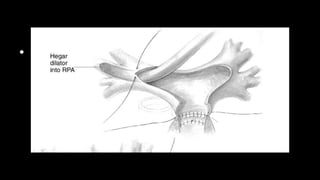

• Figure 4 Attention is now directed toward the RVOT and pulmonary valve. The pulmonary

valve is inspected and the number of cusps, their

consistency, the level of fusion, thickness, and the depth of the sinuses of Valsalva are

noted. A Hegar dilator is passed to measure the effective

orifice, NOT to dilate the valve. The cusps are thinned out gently, and each commissure is

incised with a no. 15 scalpel blade down to the

medial layers. Measure of the new effective orifice is now done again with Hegar dilators.

These maneuvers usually gain an additional 1-2 mm

in effective orifice diameter. Depending on the theoretical pulmonary annular size in

relation to the body surface area, a decision is made

about whether to stop or proceed with balloon dilation or pulmonary valve patch

augmentation. A rough estimate is that if the effective orifice

is within 1 mm of expected effective orifice for body surface area, nothing else is done. If

the effective orifice is o2 mm from expected, slow

and deliberate hand-controlled balloon dilation (Fig. 5) using as a first balloon diameter the

size of the orifice measured after sharp

commissurotomy. If the orifice is considered too small and an incision across the

pulmonary annulus is deemed necessary, then patch

augmentation of the pulmonary valve by division of the pulmonary annulus and anterior

cusp in the midline, using the 2 divided halves of the

anterior cusp to anchor the patch, is done (Fig. 6). PA = pulmonary artery.